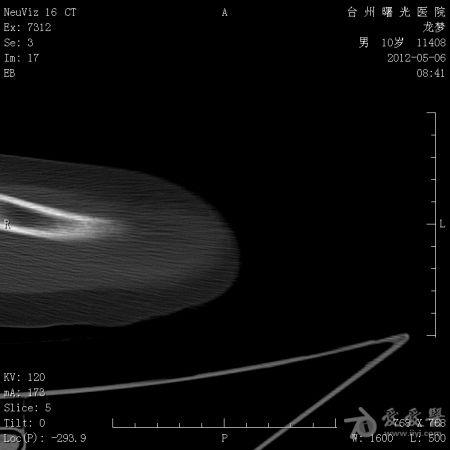

年龄:10岁主诉: 右上臂疼痛活动受限20余天现病史: 20余天前摔伤致右肘部疼痛活动不利,曾在外院治疗,X线:右肘部未见明显异常。肘关节活动尚可,于活血化瘀,消肿止痛治疗。20余天疼痛未见明显好转,肘关节活动不利,***就诊。既往史: 既往健康

体格检查: 一般状况好,发育良好,营养中等。头颅五官胸腹未见异常。右肘部,右上臂下端肿胀,压痛、纵向叩击痛(+),局部肤温增高。肘关节固定于约40°,背伸约20°,肘屈约100°,表面无血管充盈,无色素沉着。右上肢皮肤感觉正常,右桡动脉搏动正常。

初步诊断: 左肱骨下端骨肿瘤X线检查显示左肱骨中上段有虫蚀样 低密度改变,局部硬化,可见骨膜反应,病理性骨折鉴别诊断: 动脉瘤样骨囊肿,骨结核诊疗过程:

讨论内容:患者病史极短,摔伤后检查未见明显异常,初次就诊,复诊时间间隔约16天,未留下初次就诊的X线资料,仅感觉肱骨下端较上段骨密度稍减低。

骨肉瘤多见于小儿,多发生于干骨端,常见于股骨远端和胫骨近端。骨肉瘤的X线表现:⒈骨质破坏⒉肿瘤骨⒊肿瘤软骨钙化⒋软组织肿块⒌骨膜反应和Codman三角。动脉瘤样骨囊肿多发生于10-20岁,可发生生于长骨和脊柱。动脉瘤样骨囊肿的X线表现为长骨干骺端的溶骨性、偏心性骨破坏,其偏心向外突出如气球状膨胀,病变呈局限性透亮区,边界清楚,边缘有狭窄的硬化带,其中有不规则的分隔,呈蜂窝状。位于骨中心者,向周围扩张膨胀,呈卵圆形,与骨的纵轴一致。囊肿表面有一薄的骨壳,可有一层薄的骨膜反应。位于脊椎的病变多在脊突、椎板、横突上,亦可膨出于骨外。 根据以上特点和本病例的表现,骨肉瘤可疑。